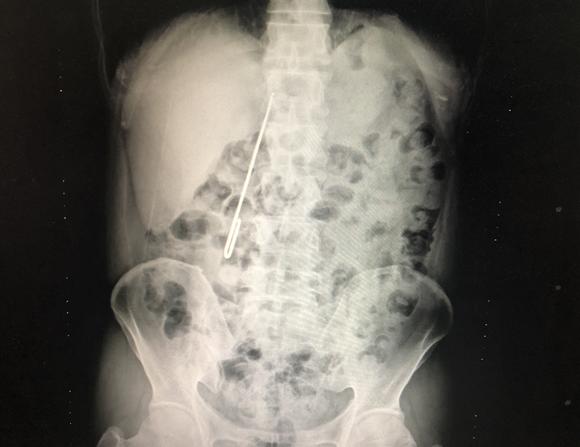

经过该科接诊的吕波医生细致检查,通过CT结果显示,毛衣针在体内十二指肠降部与水平部拐弯交界处已穿透十二指肠,尖锐一端在十二指肠外露着,针尖有进一步损伤大血管及结肠风险引起更严重后果。该科副主任医师朱新锋了解患者情况后,决定急诊手术。胃镜取出失败,并发现了十二指肠穿孔,遂只能进行手术治疗。术中将胃切开,自胃幽门从十二指内取出毛衣针,并探查未伤及大血管及结肠,十二指肠破口约0.6厘米,遂行十二指肠穿孔修补,并减压、置入鼻空肠管、充分引流。看到取出的针,医护人员都很吃惊,针的长度达到16公分,直径也有5毫米。术后,经积极治疗,患者未出现十二指肠漏,已正常进食,在康复中。